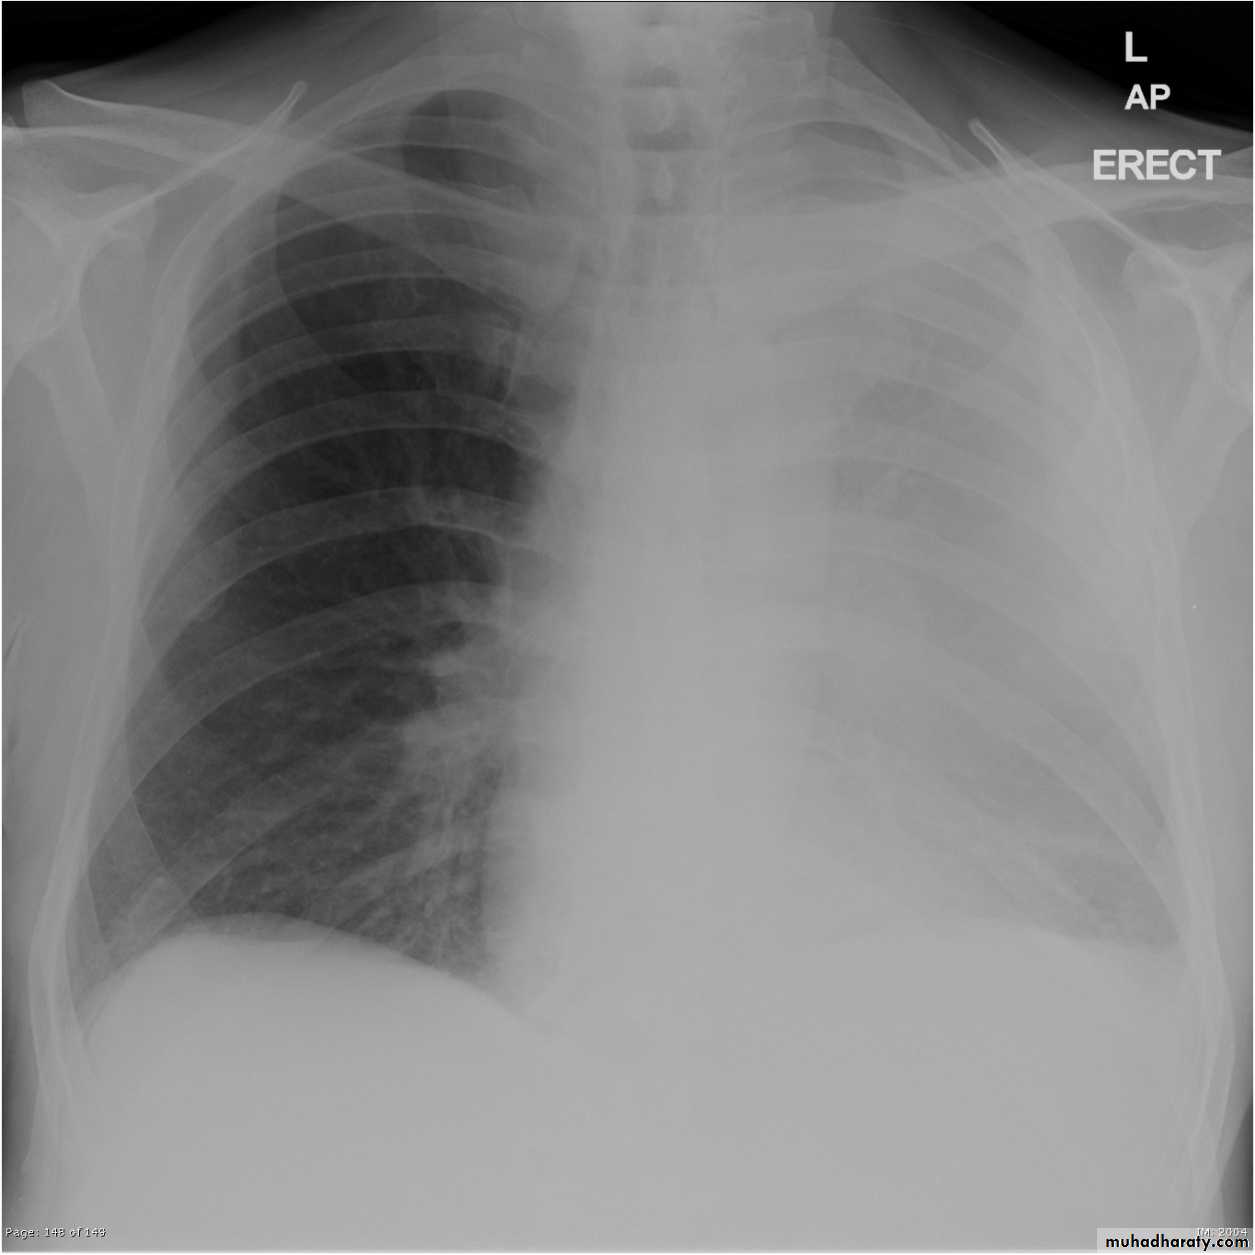

TOTAL LUNG CONSOLIDATION

Total lung collapse